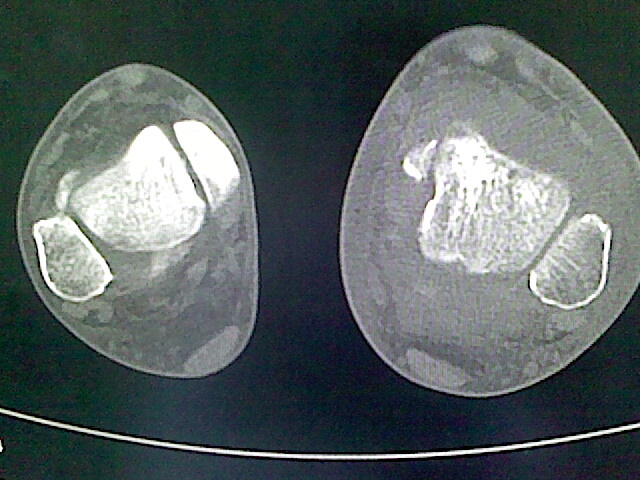

标题: CT16814:男,76岁,左小腿疼痛,不能站立 大家给看看 [打印本页]

男,76岁,左小腿疼痛,不能站立

本例骨质改变主要表现为滑膜或韧带区的骨侵蚀融解(胫腓联合区骨质破坏无硬化边),距骨后部骨质破坏区有硬化边及死骨样改变.所以,本例考虑关节结核可能性大,绒毛膜结节性滑膜炎多发于中年,且极少见于膝髋以外的关节,骨质硬坏也以压陷吸收为主,有明显的硬化边,骨膜增生呈结节状(可以mr鉴别),所以本例暂除外.

另不除外可引起相似表现的其他炎症如布氏杆菌性关节炎等